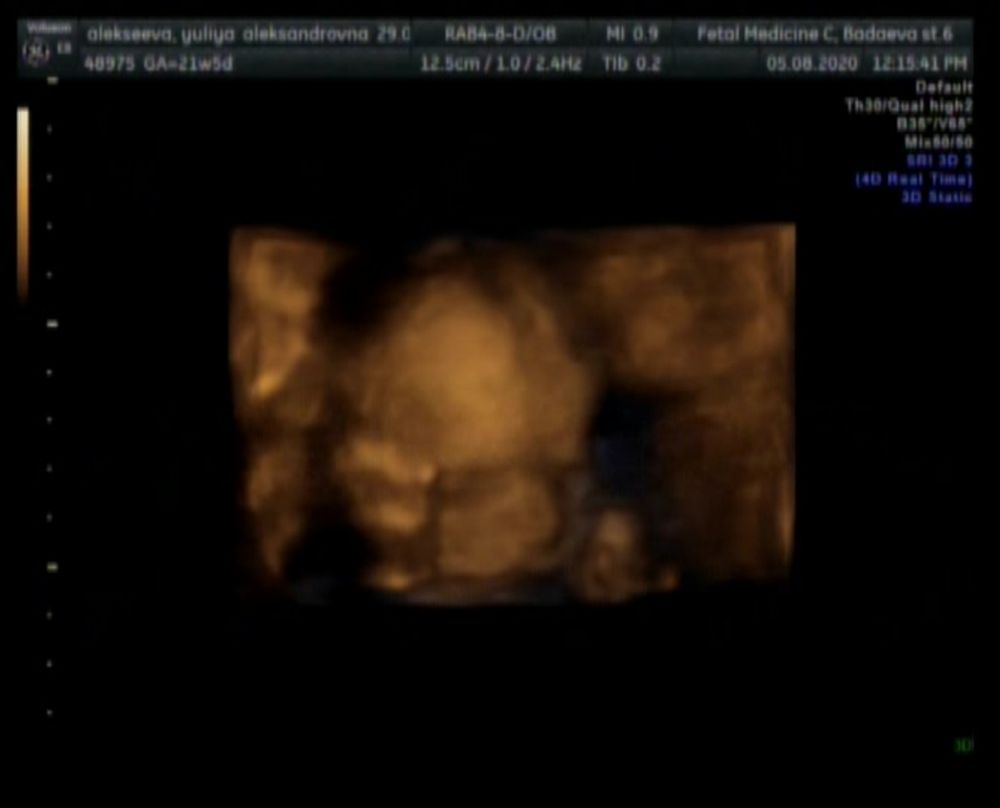

Ну, что ж, ещё одну галочку можно поставить) остаётся один скрининг, перед ним хочу сделать 3д УЗИ, чтобы с мужем сходить) Когда самое подходящее время для 3д? )

Я делаю 4д раз в 4 недели ( по показаниям). В 22 недель вообще страшненький, если честно, но черты и активность посмотреть очень интересно с мужем!

А до этого особо ничего не разглядеть - черт лица ещё нет, движения, если есть, довольно хаотичные.

Вот сейчас в 26 недели пойду делать, интересно)

Я тоже думаю примерно через 1,5 месяца, как раз в 26 недель, сходить на 3д) а то до третьего скрининга ещё ух, как далеко🤭

Делала 3д на первом скрининге и спустя 2 недели. Пока там нечего смотреть😁 Я думаю лучше ближе к третьему сделать, когда малыш массу наберёт.